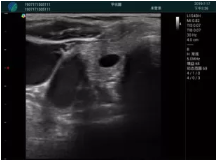

M20查看:囊內(nèi)回聲均勻,邊界清晰,囊壁光滑

M20引導抽吸術(shù)后囊腫消失,原區(qū)域空腔形成,脂肪層與腺體層架構(gòu)發(fā)生改變